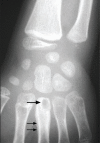

Figure 4:

Figure 4:. Date thorn infection of 3rd metacarpal. Single arrow: lytic lesion base of metacarpal; double arrow: periosteal reaction